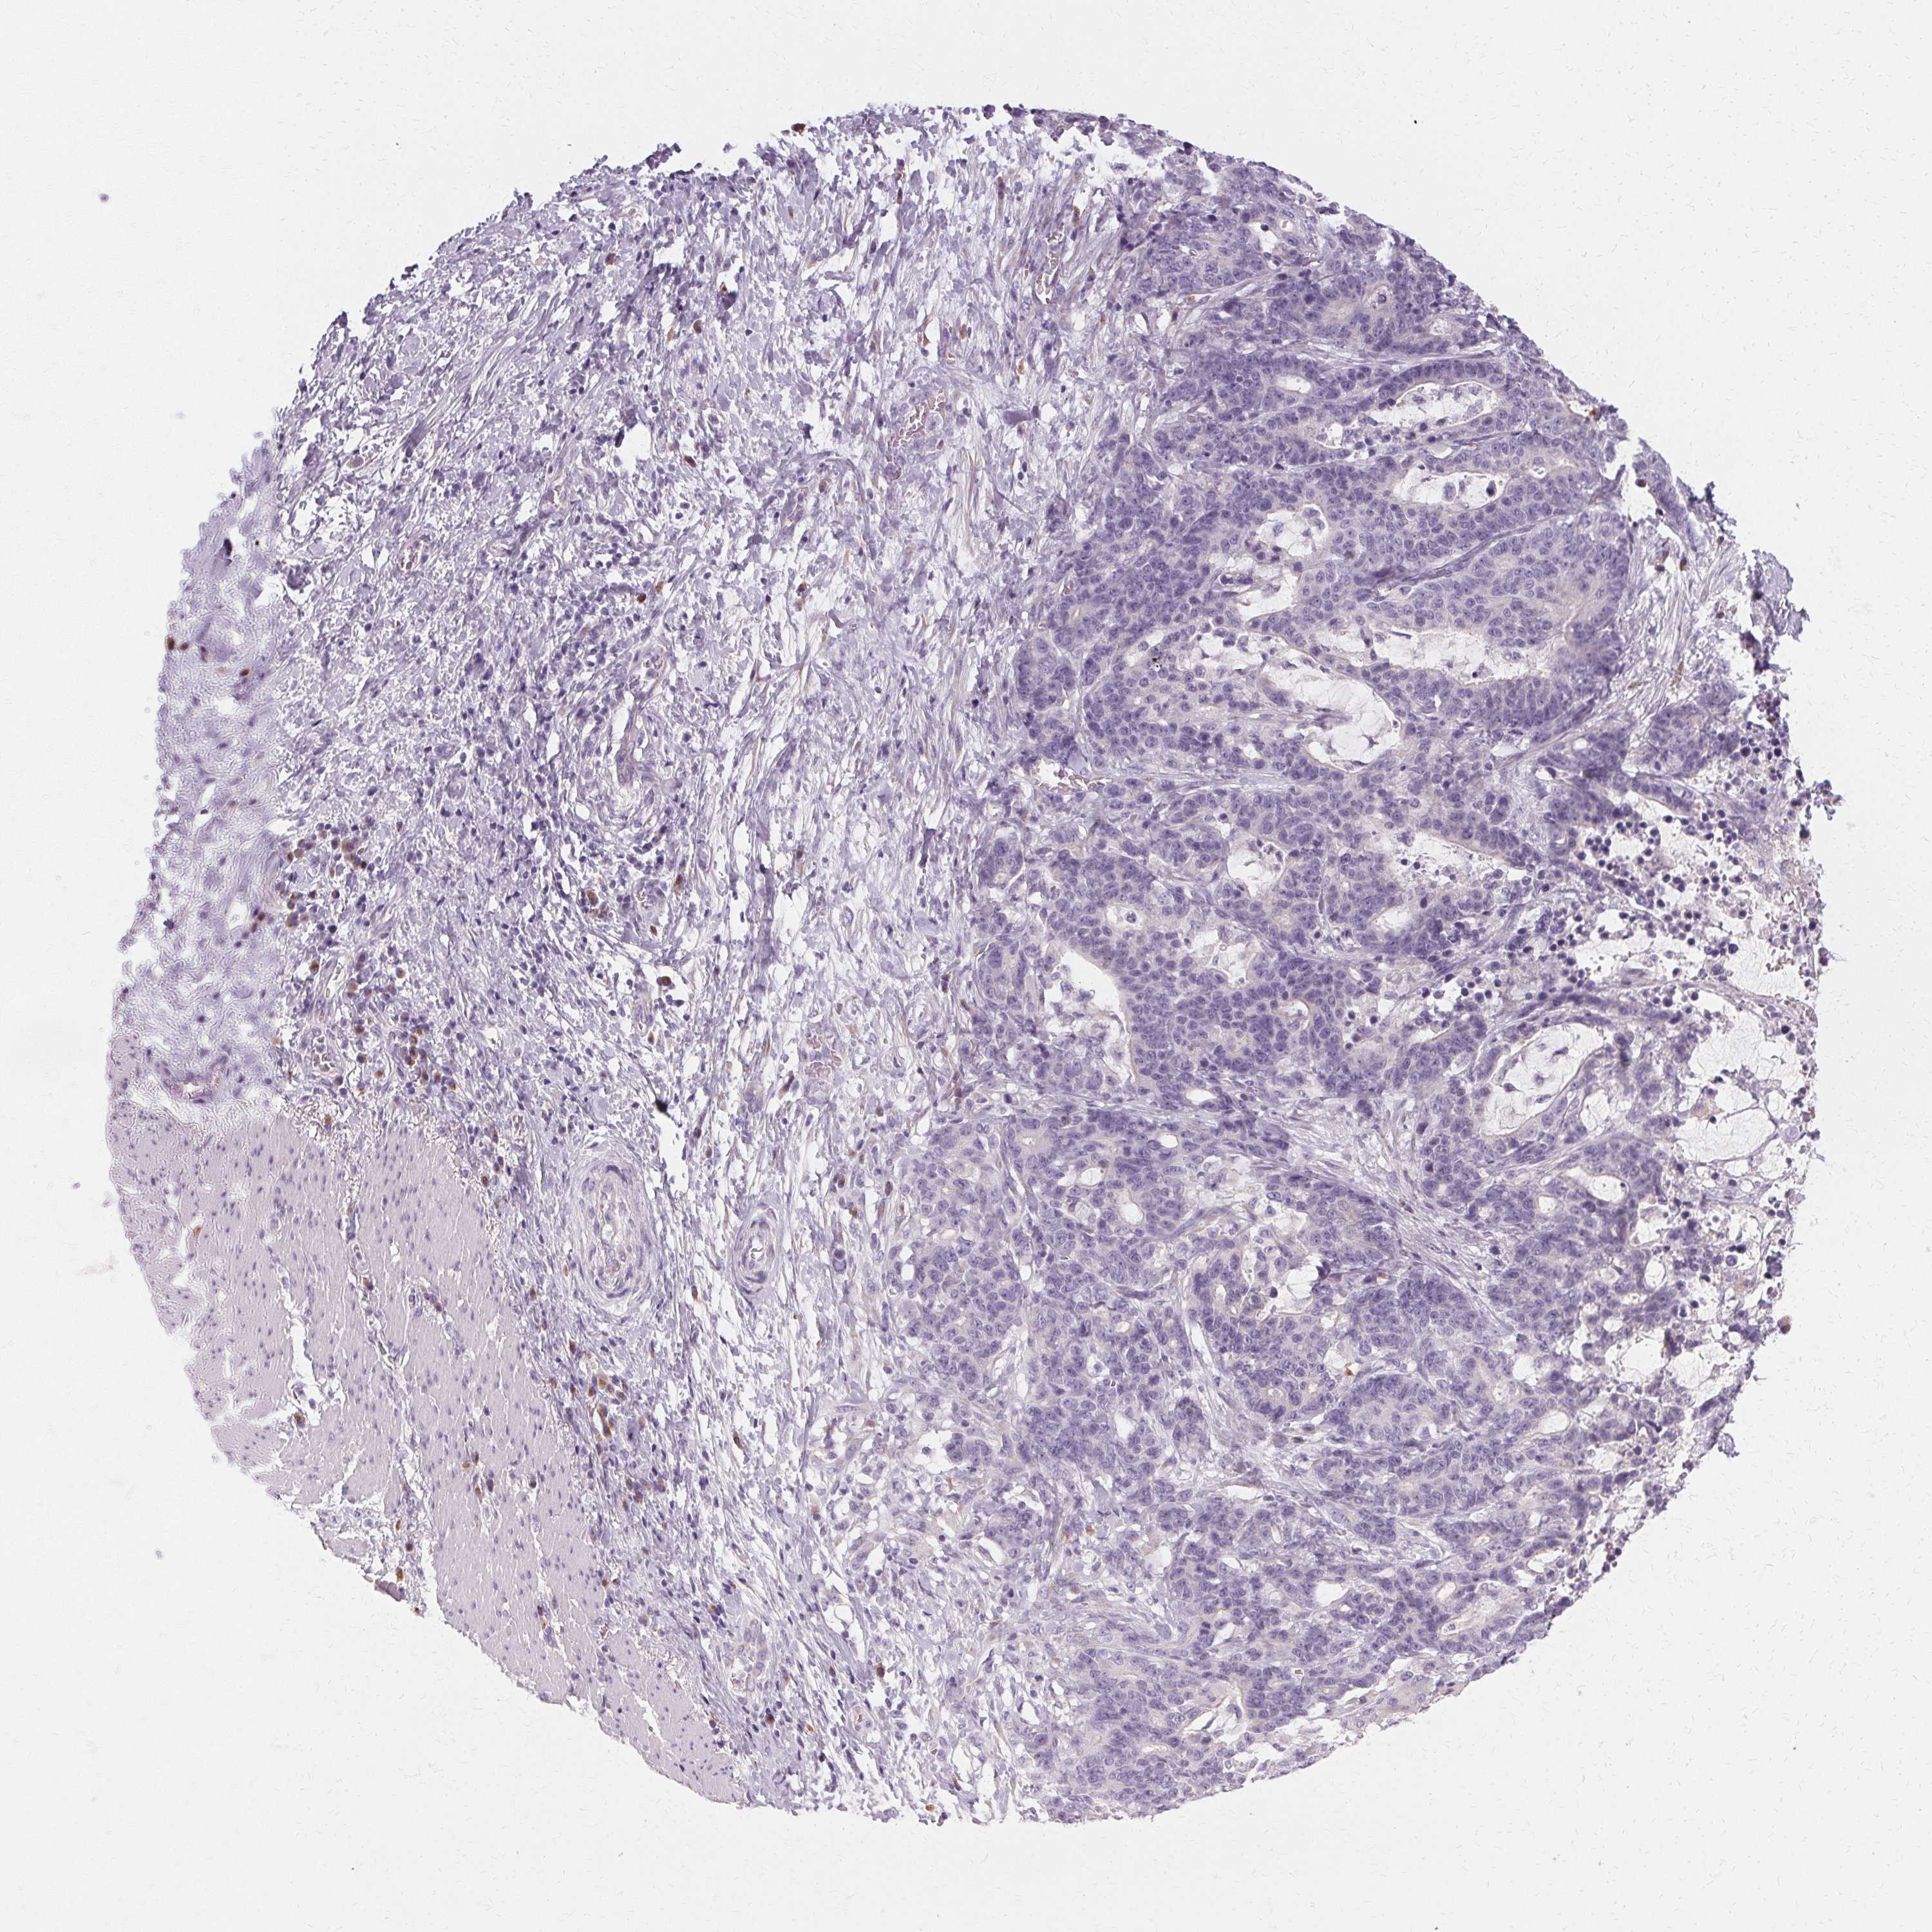

STOMACH CANCER - Protein expressioni

A mouse-over function shows sample information and annotation data. Click on an image to view it in a full screen mode. Samples can be filtered based on level of antibody staining by selecting one or several of the following categories: high, medium, low and not detected. The assay and annotation is described here.

Antibody stainingi

Antibody staining in the annotated cell types in the current human tissue is reported as not detected, low, medium, or high, based on conventional immunohistochemistry profiling in selected tissues. This score is based on the combination of the staining intensity and fraction of stained cells.

Each image is clickable and will lead to virtual microscopy that enables deeper exploration of all samples and also displays staining intensity scores, fraction scores and subcellular localization as well as patient and tissue information for each sample.

Antibody HPA048022

Staining

High

Medium

Low

Not detected

Intensity

Strong

Moderate

Weak

Negative

Quantity

>75%

75%-25%

<25%

None

Location

Nuclear

Cytoplasmic/membranous

Cytoplasmic/membranous,nuclear

Adenocarcinoma, NOS